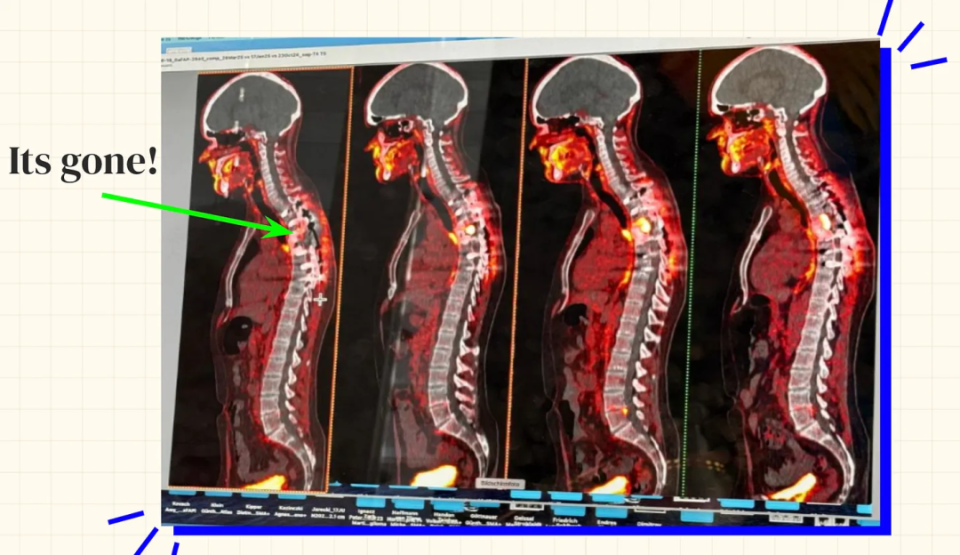

图 | 西德手术前后的癌症照片,从右至左展示了癌细胞的进展情况(来源:西德)